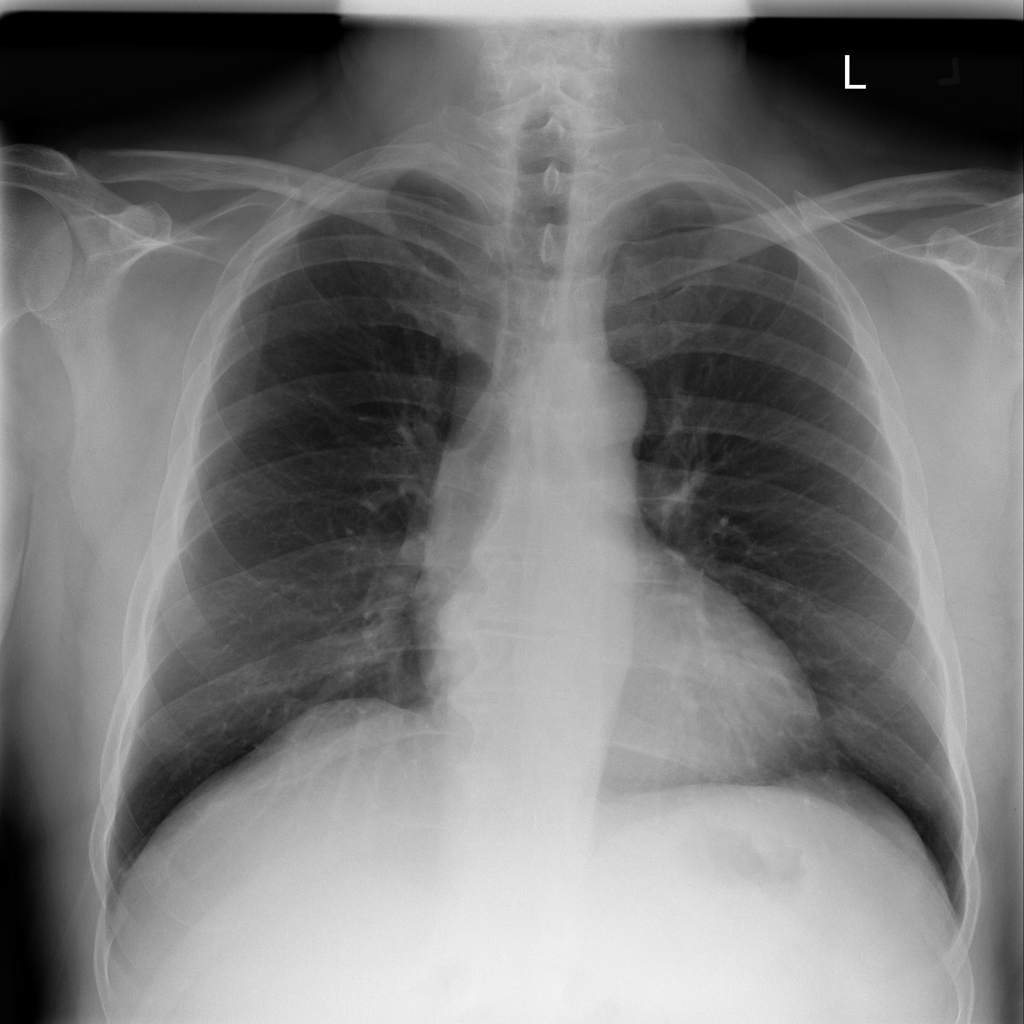

PAT-3384 · IMG-054Atelectasis

PAT-3384 · IMG-054

AP